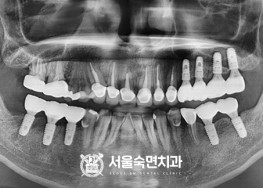

임플란트-치료-전후사진